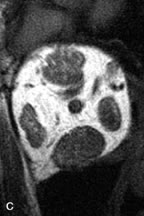

Lymphomas have MRI characteristics similar to those of inflammatory lesions in that they are hypointense to fat and isointense to muscle on T1-weighted images (Fig. 22). They may appear hyperintense to fat on T2-weighted images, perhaps owing to less fibrosis than that seen in orbital inflammatory pseudotumor, although this is not a consistent finding.31,50,66 Lymphoid tumors typically enhance moderately after contrast injection. Unfortunately, studies have shown that tumor density and homogeneity are similar between inflammatory and malignant orbital infiltrates, and MRI cannot differentiate these lesions.72,73

Fig. 22. A and B. T1- and (C) T2-weighted MR scans demonstrate a poorly defined multicompartmental mass enveloping the lateral rectus, superior rectus, and levator palpebrac superioris muscles. The lesion is isointense to brain on T1- and T2-weighted scans, as is typical for highly cellular neoplasms. D. Postcontrast fat-suppressed T1-weighted scan demonstrates intense enhancement of the infiltrating intraconal and extraconal tumor.